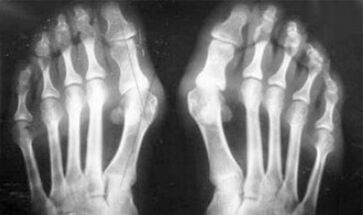

La diferencia entre la artritis y la artrosis de los dedos y las manos de las manos es que la primera enfermedad se cura y la segunda no. Con la artritis, se toca la carcasa sinovial y la cápsula de la articulación.

La derrota del cartílago y el tejido óseo ocurre solo en las últimas etapas en un estado descuidado. Con la artrosis, el tejido del cartílago se ve afectado primero, y luego el hueso, la inflamación de la membrana sinovial es de origen secundario, es decir, se desarrolla contra sus antecedentes.